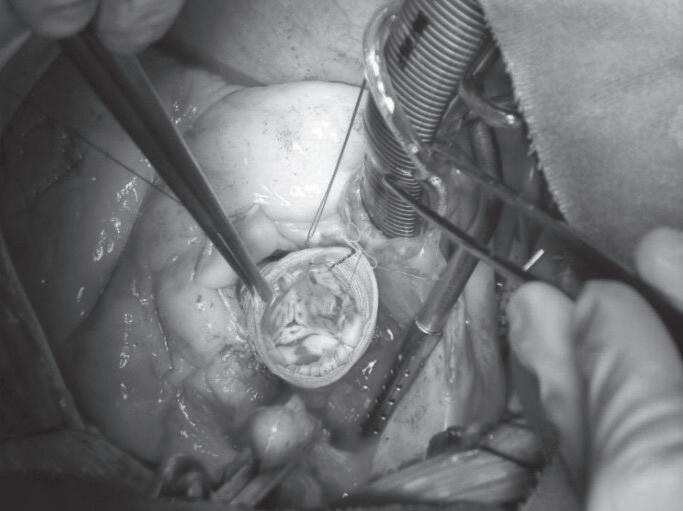

Na técnica de remodelamento de Yacoub (Fi gura 7.4), a aorta ascendente e os seios são subs tituídos por uma prótese tubular de interposição de dácron, que é fendido (“escalopado”) para incor porar os pilares comissurais da válvula aórtica.35 Os óstios coronários são então reimplantados. Como

FIGURA 7.2 (A a C) Esquema cirúrgico para o tratamento de aorta ascendente com preservação da válvula aórtica (A). Preservação da válvula aórtica e preparo do coto proximal (B). Interposição de tubo reto no segmento da aorta ascendente acima da junção sinotu bular até o início do tronco braquiocefálico (C) B C FIGURA 7.3 (A e B) Imagens demonstrativas da aplicação da técnica de David A B